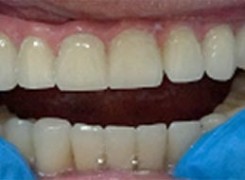

Pan Ryszard trafił do Naszego Gabinetu z jasno sprecyzowanym oczekiwaniem. Miał 84 lata i chciał odzyskać możliwość swobodnego spożywania posiłków oraz poprawienia sobie komfortu życia a także prosił aby przywrócić mu piękny uśmiech jakim cieszył się przed laty. Już na początku pierwszej rozmowy zastrzegł, że interesuje go wyłączenie rozwiązanie uzupełnieniem protetycznym stałym. Nie miał zamiaru użytkować żadnych protez ruchomych. Mając na uwadze powyższe wykonaliśmy Panu Ryszardowi zdjęcie pantomograficzne oraz badanie tomograficzne szczęki i żuchwy na postawie których zapanowywaliśmy Pacjentowi optymalne rozwiązanie – stałe uzupełnienie protetyczne w postaci 28 koron cyrkonowych zamontowanych do dwóch belek cyrkonowych które będą przymocowane do 16 implantów w konfiguracji 8 wszczepów w szczęcie 8 w żuchwie. Po omówieniu powyższego planu przystąpiliśmy do Wspólnej pracy której efekty w poszczególnych etapach prezentujemy poniżej.